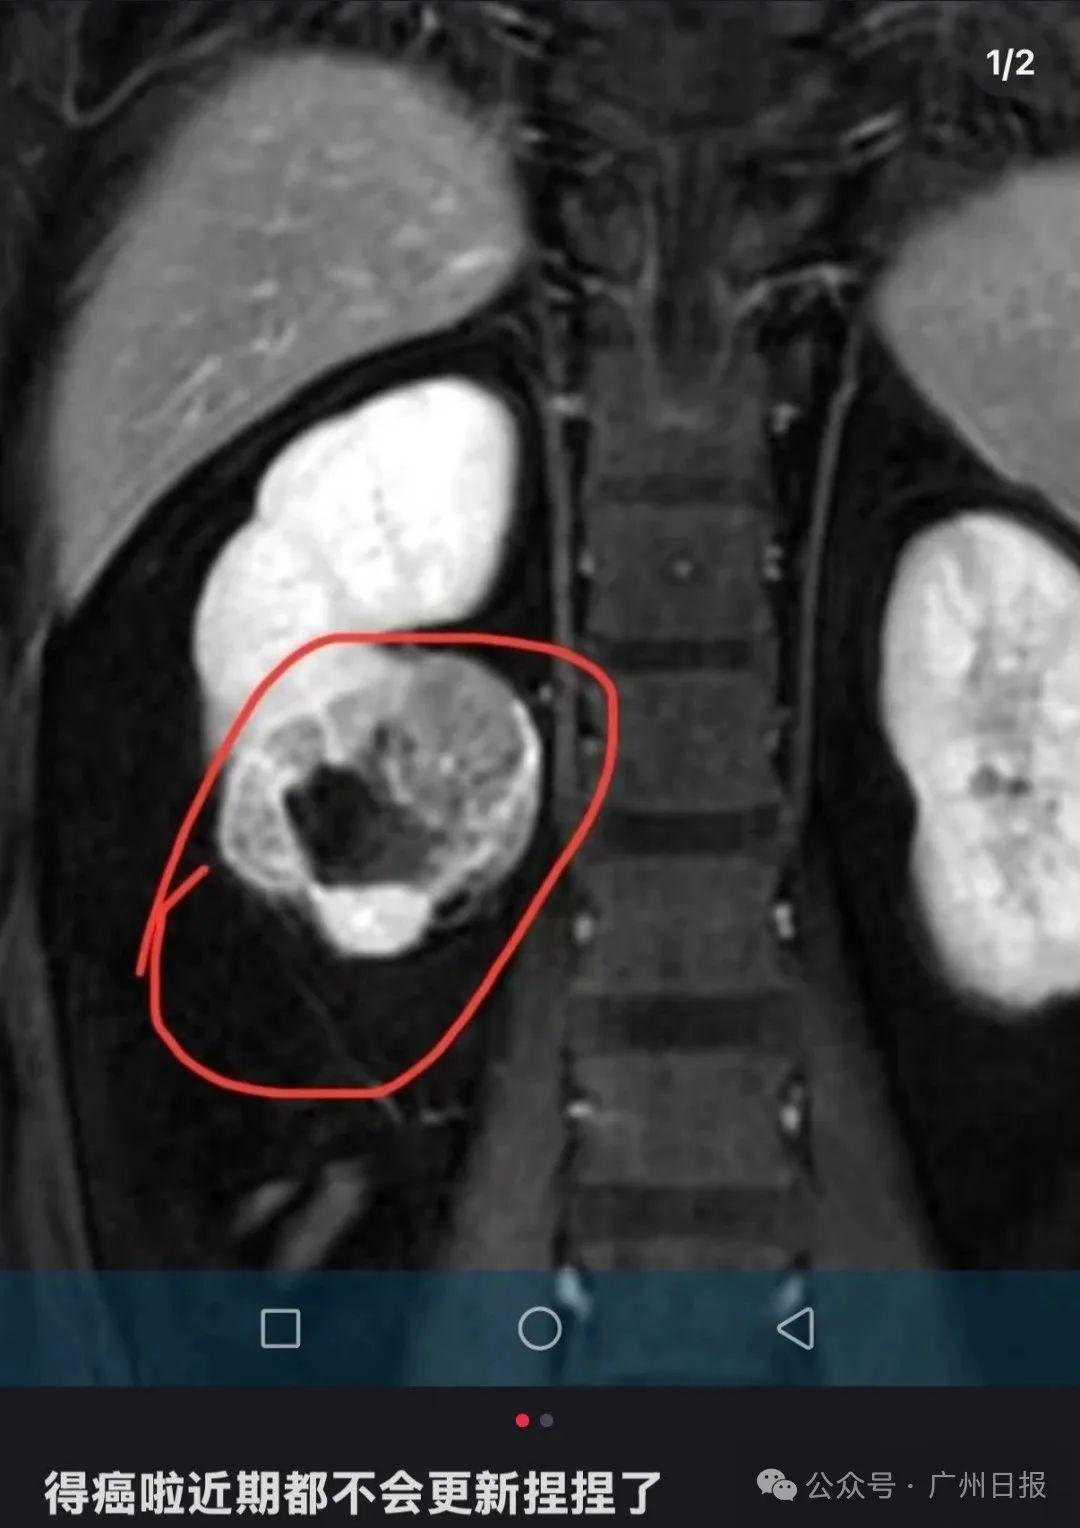

近兩年一種捏後能回彈的玩具“捏捏”走紅成爲年輕人緩解壓力的熱門選擇然而近日一位解壓“捏捏”玩具博主自曝患癌的消息令公衆對於“捏捏”玩具潛在健康風險的擔憂進一步加劇該博主在社交媒體上發文透露自己罹患腎癌,並宣佈將暫時停止更新與“捏捏”玩具相關的視頻內容。該博主最新更新透露病情:腎臟有部分壞...